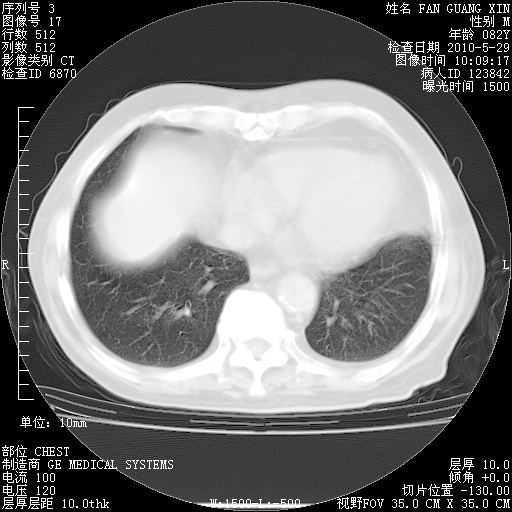

再治疗10天后的肺部CT

阅读此次胸部CT,肺间质渗出性改变较入院时有吸收。目前从体温、白细胞、中性分叶明显增高,肯定存在细菌感染(发生医院感染哦,若无消化道及泌尿系统等感染的依据,肺部感染可能大)。若你院头孢哌酮舒巴坦钠耐药率较高,同意你的方案,若48小时体温仍高,可考虑使用碳青霉稀类抗菌药物,同时可予超声雾化、注意滴数时加大液体量。白蛋白33.30g/L较低哦,需加强营养等支持治疗。